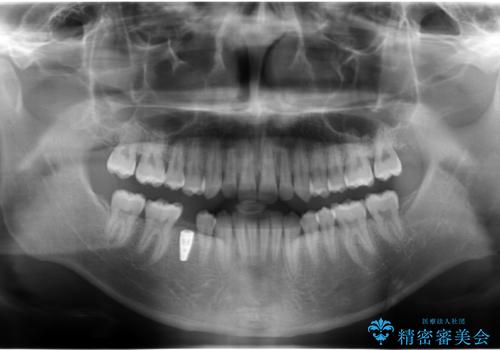

- 当院で矯正治療後、奥歯(前から5番目の歯)のインプラントを行いました。

元々乳歯が残っており、永久歯が欠損していました。

また、一番後ろの永久歯(7番目)の周りに骨がたくさんあり、そこの骨の形を整えて削ってあげたほうが、7番目の歯がしっかり歯茎の炎症も治りやすい状況でした。

そのため、5番目のインプラントと、7番目の骨整形を同時に行い、整形で取れた7番目の骨をインプラント周囲に移植し、骨を増やすことにしました。

矯正治療の経過は以下に示しています。